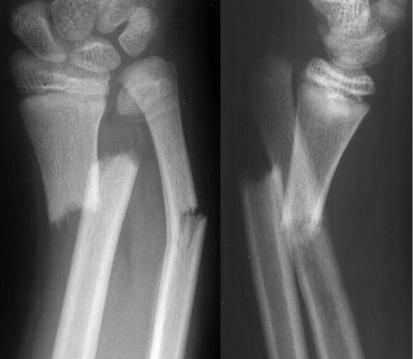

5. Интерпретация рентгенограммы с заболеваниями и

повреждениями опорно-двигательного аппарата (пример) (рис. 7)

Рис. 7. Рентгенограмма пациента с переломом нижней обеих костей предплечья со смещением.